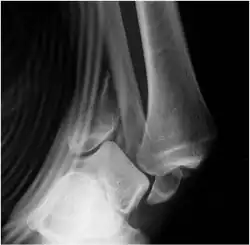

Der Bruch des oberen Sprunggelenks entsteht immer über eine mehr oder weniger starke Verrenkung (Subluxation oder Luxation) des Gelenks, d. h. eine Lösung der Knochen des Gelenks aus ihrer normalen gelenkigen Verbindung unter Bruch von mindestens dem Außenknöchel und möglichen knöchernen und ligamentären Begleitverletzungen. Daher heißt die Verletzung grundsätzlich Verrenkungsbruch (Luxationsfraktur). Zur Illustration ist eine Sprunggelenkfraktur noch in Verrenkungsposition abgebildet. Meist reponieren sich die Brüche aufgrund der Elastizität des Weichteilmantels von alleine, oder sie werden durch Sanitäter oder Sporttrainer noch am Unfallort reponiert, so dass solche Röntgenbilder selten in Kliniken entstehen. Der Verletzung, volkstümlich als „Umknicken“ bezeichnet, liegt meist ein Pronationstrauma oder eine Supination zugrunde (beides indirekte Traumata). Dieses Grundmuster wird durch Drehungsanteile (z. B. Eversion, Adduktion) des Fußes ergänzt. Der Sprunggelenkbruch kann auch durch Drehen des Unterschenkels gegen den feststehenden Fuß verursacht werden. Häufig sind zusätzlich die Einflüsse von Stauchungen wirksam, wie z. B. durch den Sprung von einer Mauer. Das röntgenologische Bruchbild lässt sich nach Lauge-Hansen[2] einem jeweils typischen Entstehungsmechanismus zuordnen (= ursächliche Einteilung).

Die Diagnostik erfordert neben der Erhebung der Vorgeschichte (Anamnese) und der klinischen (körperlichen) Untersuchung eine Röntgenuntersuchung. Sie wird im a.p. (anterior-posterioren) Strahlengang mit 20° Innenrotation sowie im seitlichen Strahlengang angefertigt. Mit Schrägaufnahmen im Winkel von 45° können Ausrisse am Syndesmosenansatz des Schienbeins (franz. Tubercule de Chaput Tillaux) erkannt werden. Im Zweifelsfall muss immer auch eine Langaufnahme zum Ausschluss einer hohen Wadenbeinfraktur (Maisonneuve-Fraktur) angefertigt werden.[3] Die im Röntgenbild unsichtbaren Verletzungen der Bänder werden bei Verdacht nach Einleitung der Narkose, aber vor Beginn des eigentlichen operativen Eingriffs durch eine gehaltene Röntgen-Bildwandleruntersuchung aufgedeckt.